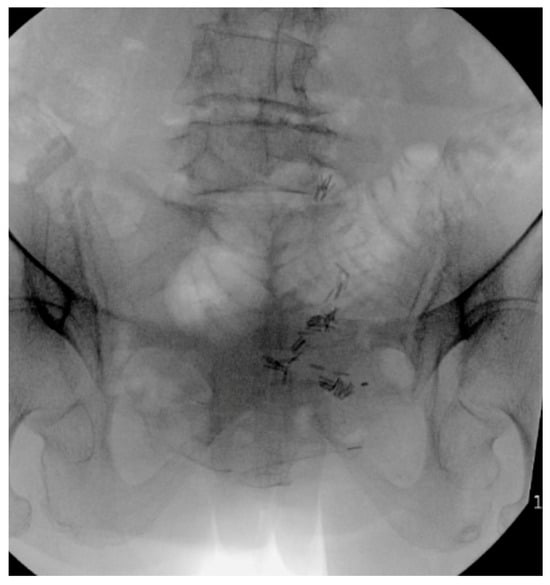

Minimally Invasive and Navigation-Assisted Fracture Stabilization Following Traumatic Spinopelvic Dissociation

6. Spinopelvic Fixation Percutaneous Technique

7. Tran-Sacral Percutaneous Technique